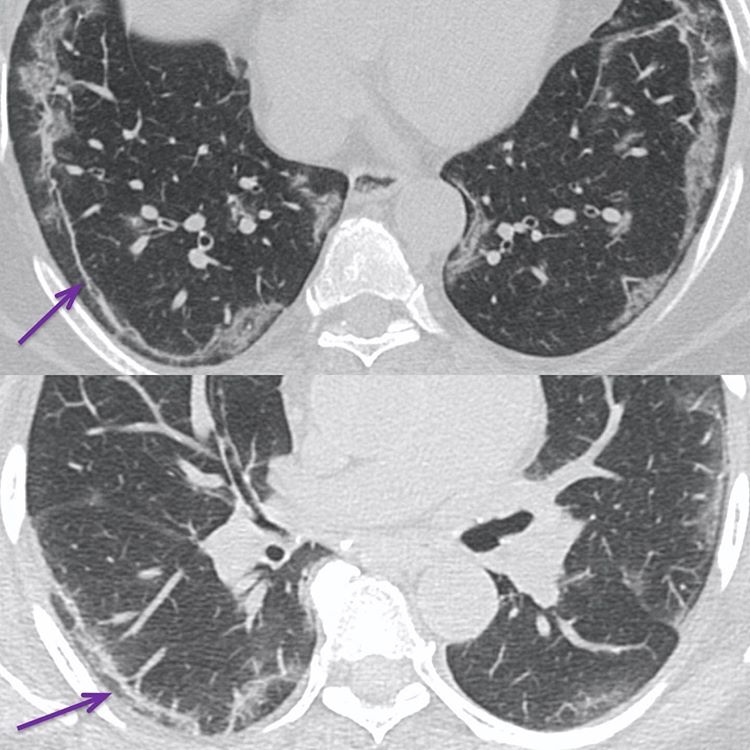

Many patients show thin or thick curvilinear bands (purple arrows) usually in the lower lobes in the posterior and lateral basal segments. It is not clear what they represent. Some say that they are due to resolving pneumonia, but we have seen these bands at first presentation as well. Others believe they are due to sub-segmental atelectasis, because of their location and yet some others believe they represent fibrosis, though we have seen these bands resolve as well.

Perhaps they are a combination of multiple things – partly resolving pneumonia with an element of sub-segmental atelectasis and perhaps an element of fibrosis in some patients.